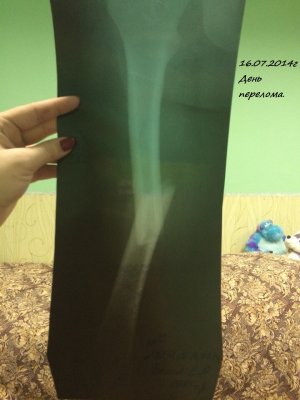

Здравствуйте! Мне 19 лет. 16.07.2014 года у меня случился закрытый перелом с/3 правого бедра со смещением. Произошло это так: я решила заниматься бегом. Каждый день бегала по стадиону минут 30-40. Получилось так, что я бежала, потом споткнувшись правой ногой, вернее как только я споткнулась, услышала хруст и упала на левую сторону. Сначала вообще не поняла, что произошло. Попыталась пошевелить ступней, особых болевых ощущений не испытала и решила попробовать встать, как только я попыталась поднять ногу, я увидела как у меня в бедре "шевелятся" кости. В итоге вызвали скорую, сделали рентген (все снимки я загрузила), поставили спицу под б/берцовую кость, почти под коленом, и я лежала 6 дней на вытяжке. 22.07.2014 года был проведен Экстрамедуллярный остеосинтез правого бедра пластиной АО (все пишу из выписки медицинской карты)Причем, прошу заметить на снимках может быть не видно, во время операции обломалось сверло, и пластину не закрепили по краям, я, конечно, мало что понимаю. 4.08.2014 года мне наложили гипс и отправили домой. 15.09.2014 года сняли гипс, я стала постепенно разрабатывать ногу, ходить, примерно 1.10.2014 года я стала ходить с тростью, все вроде бы шло на поправку. 23.10.2014 года меня выписали, и я уехала учиться в ВУЗ. Примерно вначале декабря я упала с лестницы(примерно со 2-ой ступеньки, при этом все это время я ходила с тростью). Стала болеть нога, я пошла в больницу, вновь снимок. Сказали все нормально-срастается. Назначили магнит(10 дней), отходила я на магнит. Все стало нормально, после НГ я могла ходить без трости, немного хромала, носила ее с собой, и когда уставала-ходила с ней. Вначале марта, примерно с 5-ого числа, стали мучить очень сильные боли, причем болело колено, очень тянуло берцовые кости, иногда беспокоило место перелома, вновь иду в больницу, опять снимок. И УЖАС! На снимке видно, как у меня кривится кость, чуть ли не ломаясь пополам, и переломана пластина. Мне говорят, что нужно делать операцию, врач сказал, что пластину не будут ставить повторно, эту уберут, все почистят и поставят штифт.